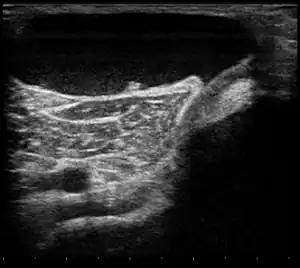

| Ultrasound image of Baker's cyst[2] | |

Risk factors include other knee problems such as osteoarthritis, meniscal tears, or rheumatoid arthritis.[1][4][5] The underlying mechanism involves the flow of synovial fluid from the knee joint to the gastrocnemio-semimembranosus bursa, resulting in its expansion.[1] The diagnosis may be confirmed with ultrasound or magnetic resonance imaging (MRI).[4]

Diagnosis is by examination. A Baker's cyst is easier to see from behind with the patient standing with knees fully extended. It is most easily palpated (felt) with the knee partially flexed. Diagnosis is confirmed by ultrasonography, although if needed and there is no suspicion of a popliteal artery aneurysm then aspiration of synovial fluid from the cyst may be undertaken with care. An MRI image can reveal presence of a Baker's cyst.